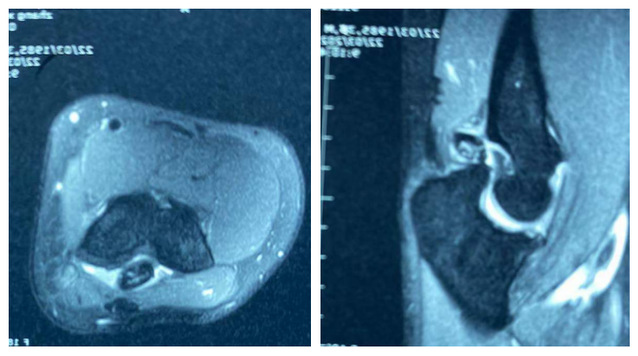

术前患者肘关节磁共振

患者男,因右肘关节疼痛伴屈伸受限约2年,严重影响了工作和生活,曾辗转周边多家医院就诊,均建议给予切开手术,后患者多方打听到齐医附属三院微创骨科专家孙文才主任专业做微创手术后,到我院就诊,肘关节MRI提示右肘后鹰嘴窝处异位骨化、关节游离体形成,入院后经孙文才主任及其团队充分讨论,决定对其实施肘关节镜微创治疗手术,采用肘后内外侧标准入路,切口仅长约0.5cm,术中创伤小、出血微量,手术实施顺利,成功将游离体及异位骨化骨块取出,术后肘关节功能恢复好,患者对治疗效果非常满意。